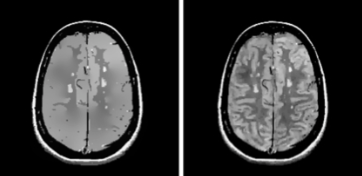

Brain MR with multiple sclerosis lesions after 500 iteration of anisotropic diffusion(left), and stabilized diffusion via s-scale (right).

Original PD brain MR image of a multiple sclerosis patient (left) followed by resulting images after applying ball scale, classical and generalized scale diffusion filtering

Zoomed in regions for the above images